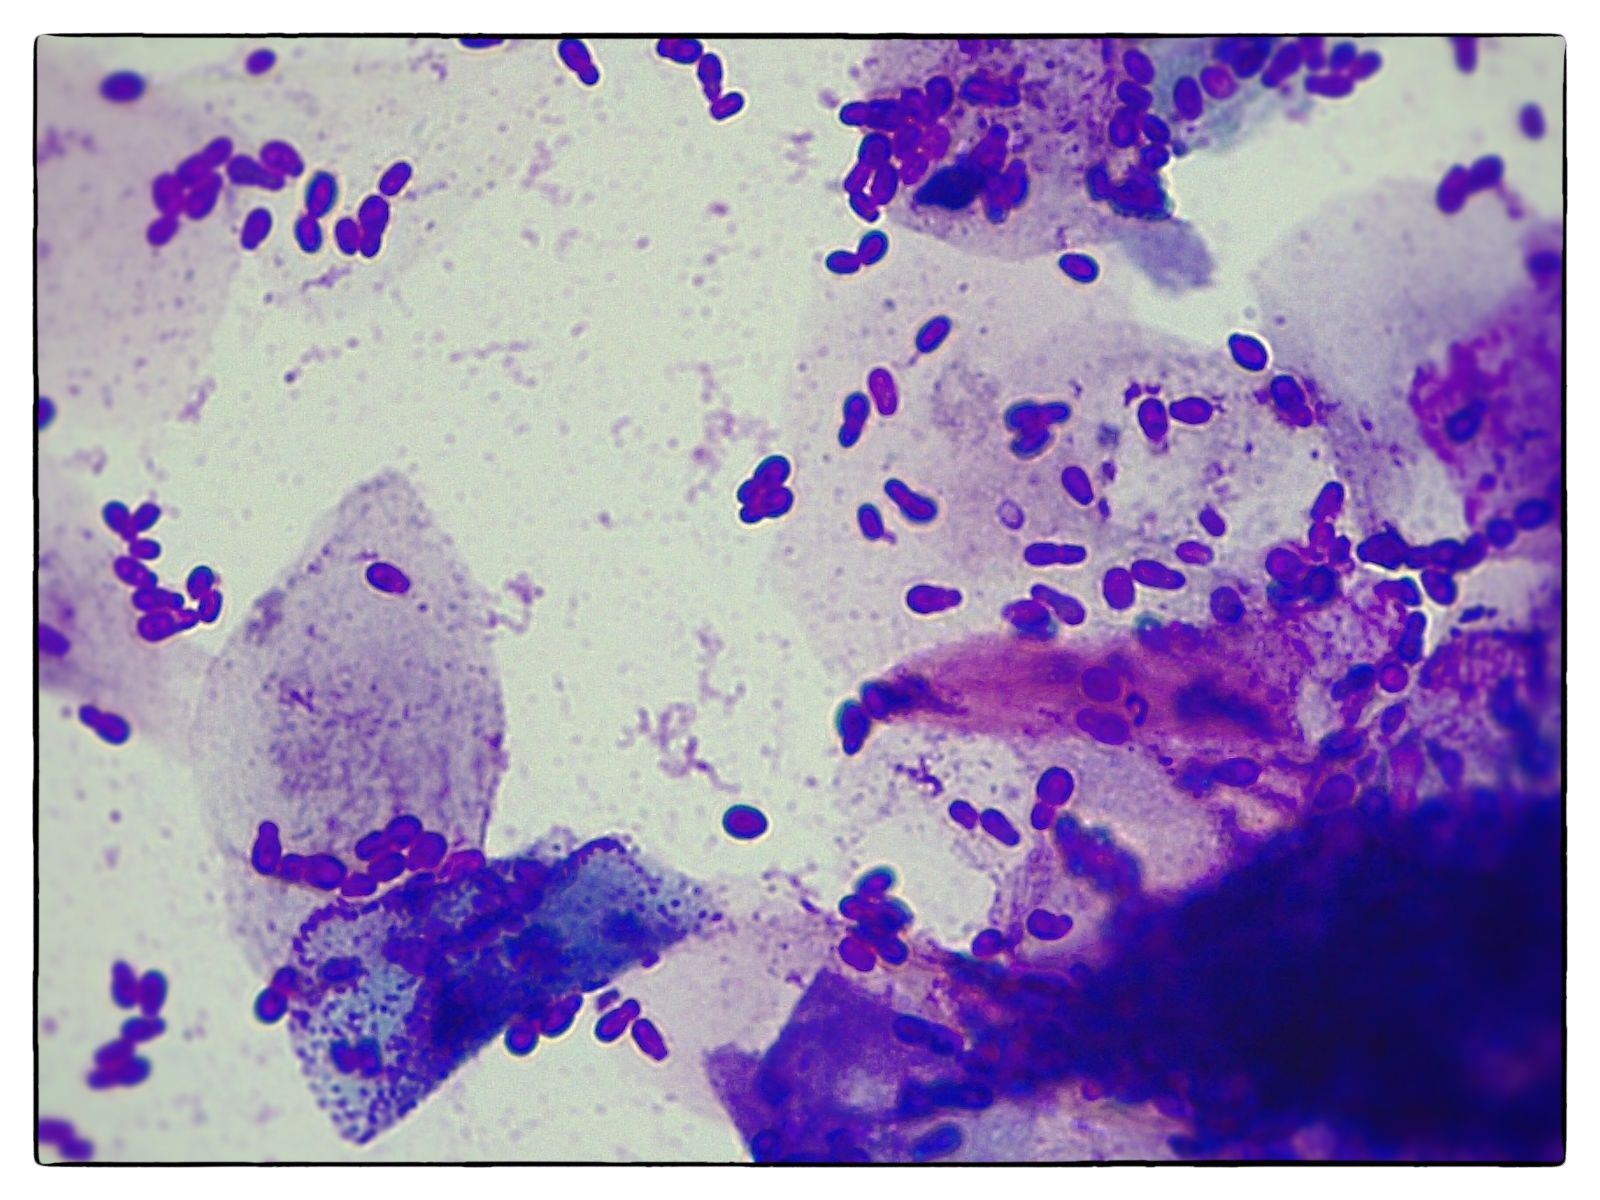

Les analyses microscopiques

Un microscope binoculaire occupe une place importante au sein de notre laboratoire. Il est directement relié à un écran d'ordinateur ce qui permet de visualiser sur grand écran et d'archiver nos lames d'examen. En fonction de l'examen, les lames peuvent être colorées par bains successifs.

- Lames en reproduction (suivi de chaleurs, spermogramme, infections génitales diverses)